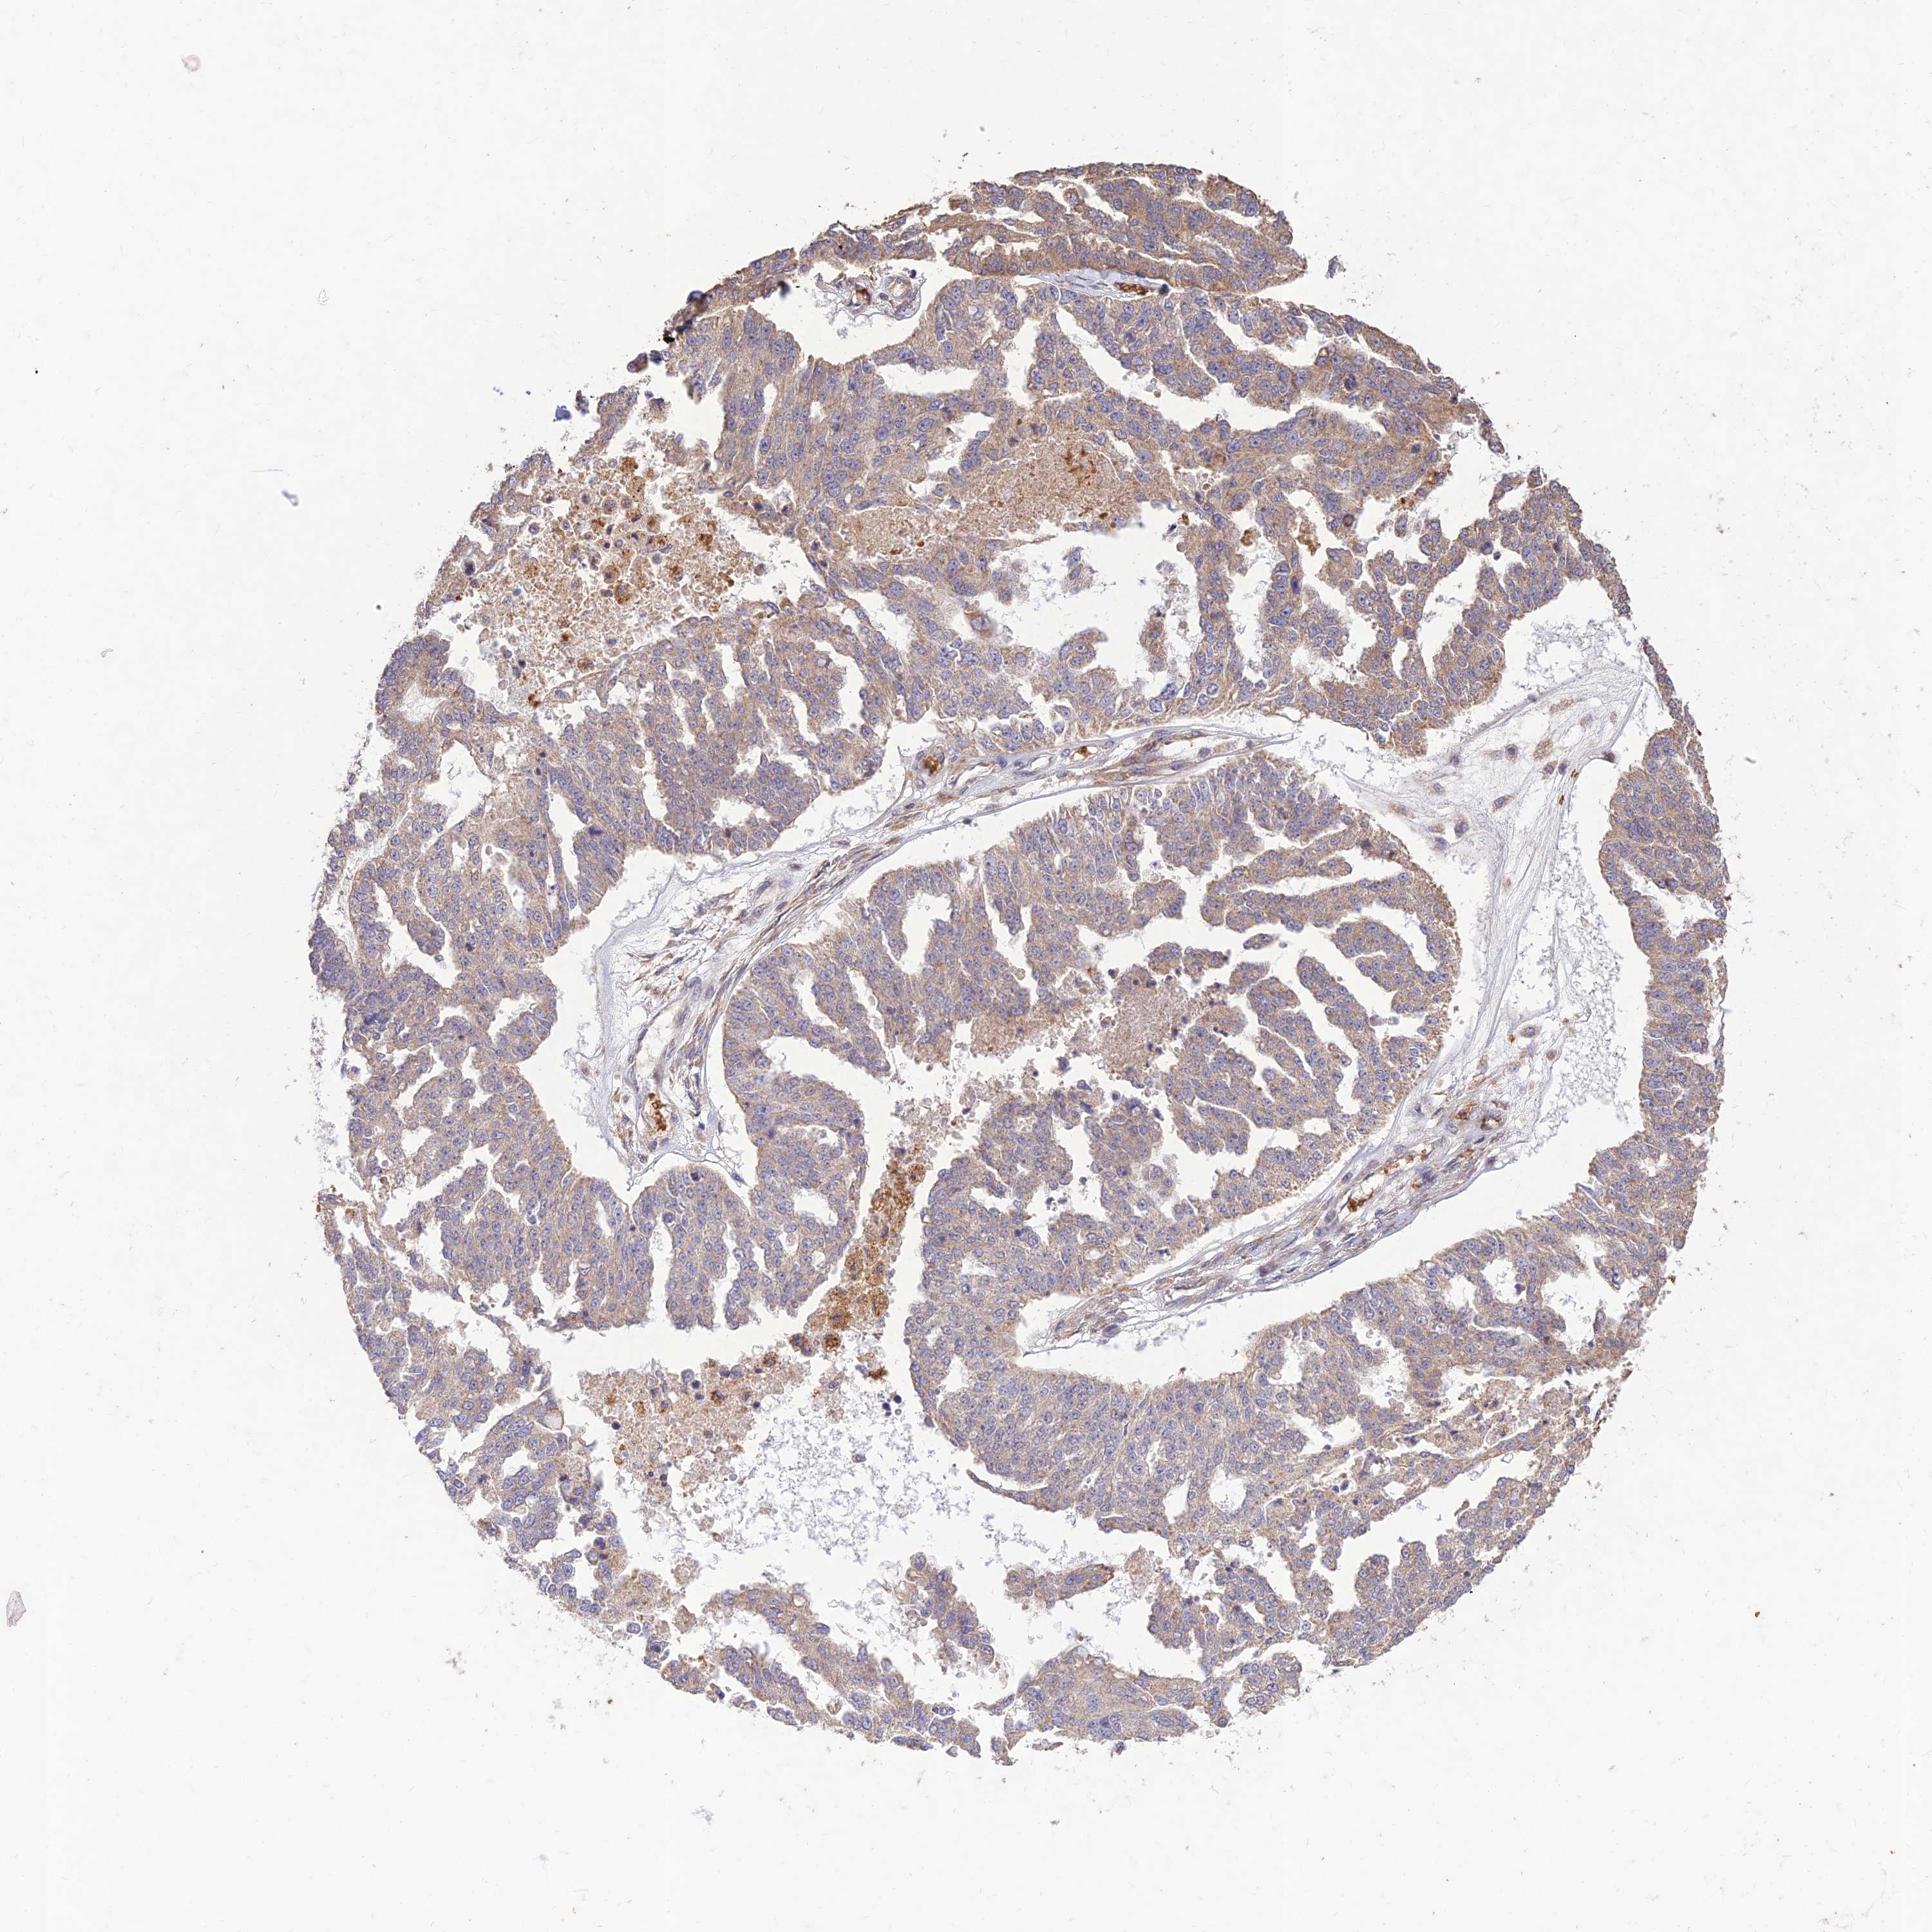

OVARIAN CANCER - Protein expressioni

A mouse-over function shows sample information and annotation data. Click on an image to view it in a full screen mode. Samples can be filtered based on level of antibody staining by selecting one or several of the following categories: high, medium, low and not detected. The assay and annotation is described here.

Note that samples used for immunohistochemistry by the Human Protein Atlas do not correspond to samples in the TCGA dataset.

Antibody stainingi

Antibody staining in the annotated cell types in the current human tissue is reported as not detected, low, medium, or high, based on conventional immunohistochemistry profiling in selected tissues. This score is based on the combination of the staining intensity and fraction of stained cells.

Each image is clickable and will lead to virtual microscopy that enables deeper exploration of all samples and also displays staining intensity scores, fraction scores and subcellular localization as well as patient and tissue information for each sample.

Antibody HPA043266

Cystadenocarcinoma, serous, NOS

Carcinoma, NOS

Cystadenocarcinoma, mucinous, NOS

Carcinoma, endometroid